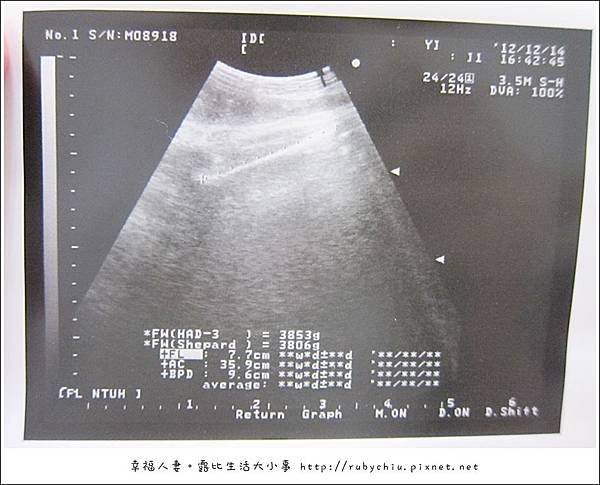

醫生照了超音波後,跟我說羊水胎盤都正常!!! 也把BABY的器官都照了一遍跟我說狀況。

非常細心的一個個說明 跟曾醫生的看診不太一樣。

頭己經9.7cm

大腿7.7cm

體重3800

醫生馬上說 週一如果還沒有產兆 一定要回診跟曾醫生商量催生!!

因為"紀念品"有點大嚕!!!